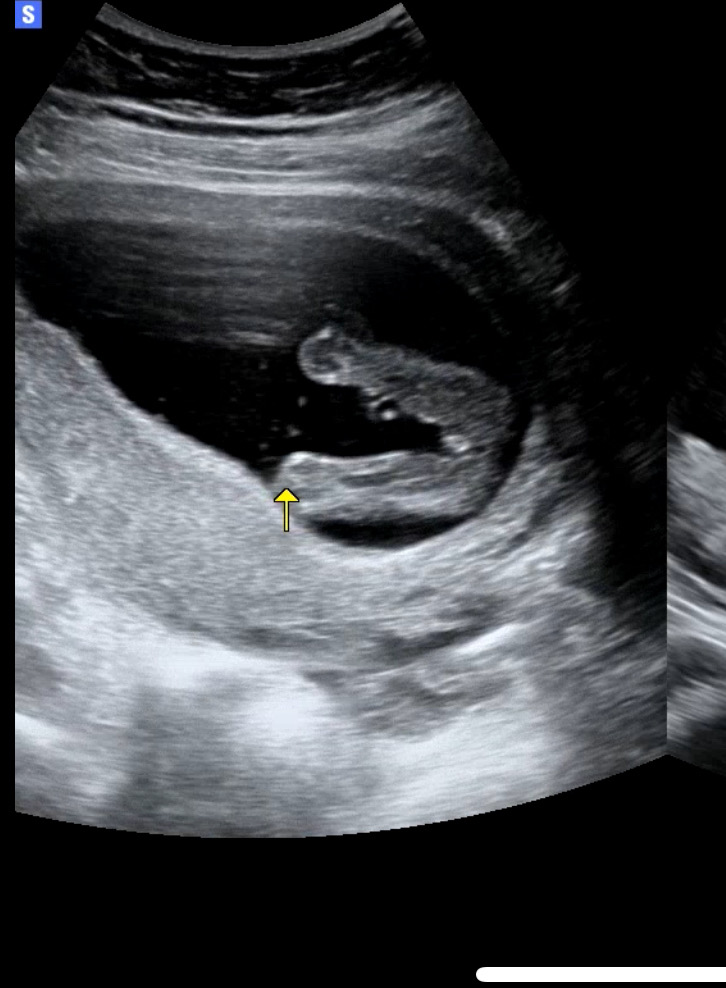

8-90프로는 딸이라고 하셧는데 성별 반전은 없겟죠??🥹 생식기도 측면에서 내려가잇엇습니다!..

네 16주 입니다!!!

16주에 확인하셨나요? 16주면 거의 반전없다고 하긴하더라구요! 사진은 딸맞는거같아요!